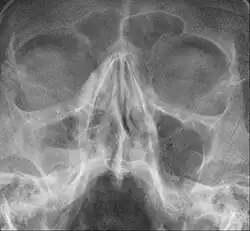

Sinusitis maxillaris rechts (also im Röntgenbild links). Man erkennt deutlich den Luft-Flüssigkeitsspiegel als Zeichen einer akuten Entzündung.